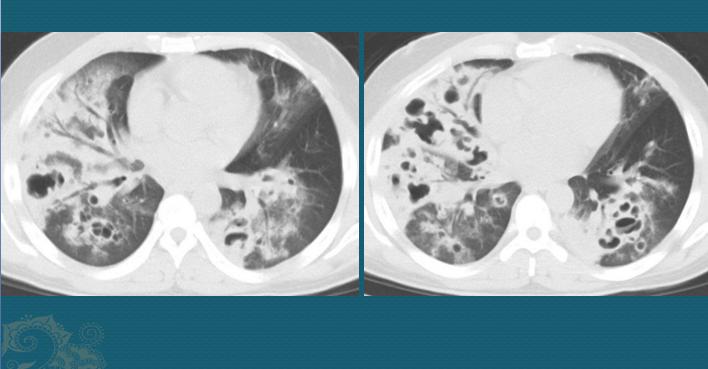

经过24的培养,金葡菌就能形成3mm的金黄色菌落,而我们人类的小气道<2mm,可以轻易被脓液堵塞。脓液比较黏稠,所以这种小气道堵塞常常是不完全性的,呈活瓣样,气体易进难出,就会发生远侧肺气囊,像气球一样吹大了。

而粘稠脓液是液态的,会随气压变化在小气管里缓慢移动,变换堵塞部位和堵塞程度,加上病变区肺组织受脓液腐蚀失去弹性(容易塌陷),这些气囊形态可以多变。所以金葡菌肺炎进展期的CT征象可以在短期内快速变化。下图是这位病人第三次复查,肺气囊和空洞进一步增多、增大:

这位病人重症肺炎,在鬼门关前转了一圈,经过20多天治疗才脱离危险。